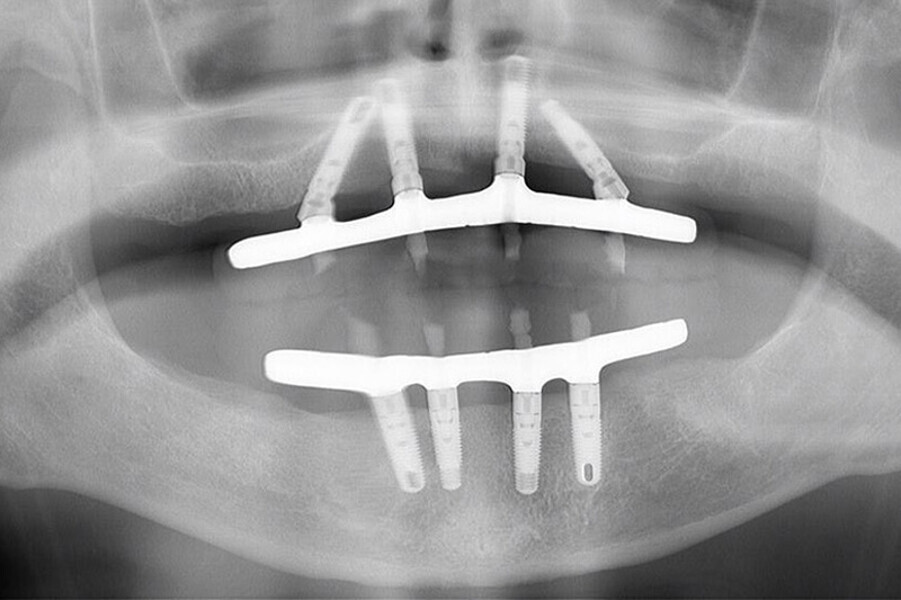

Fig. 7. Rx Pre-operatoria, Prótesis híbrida inmediata con 10 años de evolución y Rx Control a los 10 años.

Fig. 8. Rx Pre-operatoria, Prótesis híbrida inmediata con 10 años de evolución y Rx Control a los 10 años.

Fig. 9. Rx Pre-operatoria, Prótesis híbrida inmediata con 10 años de evolución y Rx Control a los 10 años.

Fig. 10. Prótesis híbrida inmediata con 10 años de evolución y Rx Control a los 10 años.

Fig. 11. Prótesis híbrida inmediata con 10 años de evolución y Rx Control a los 10 años.